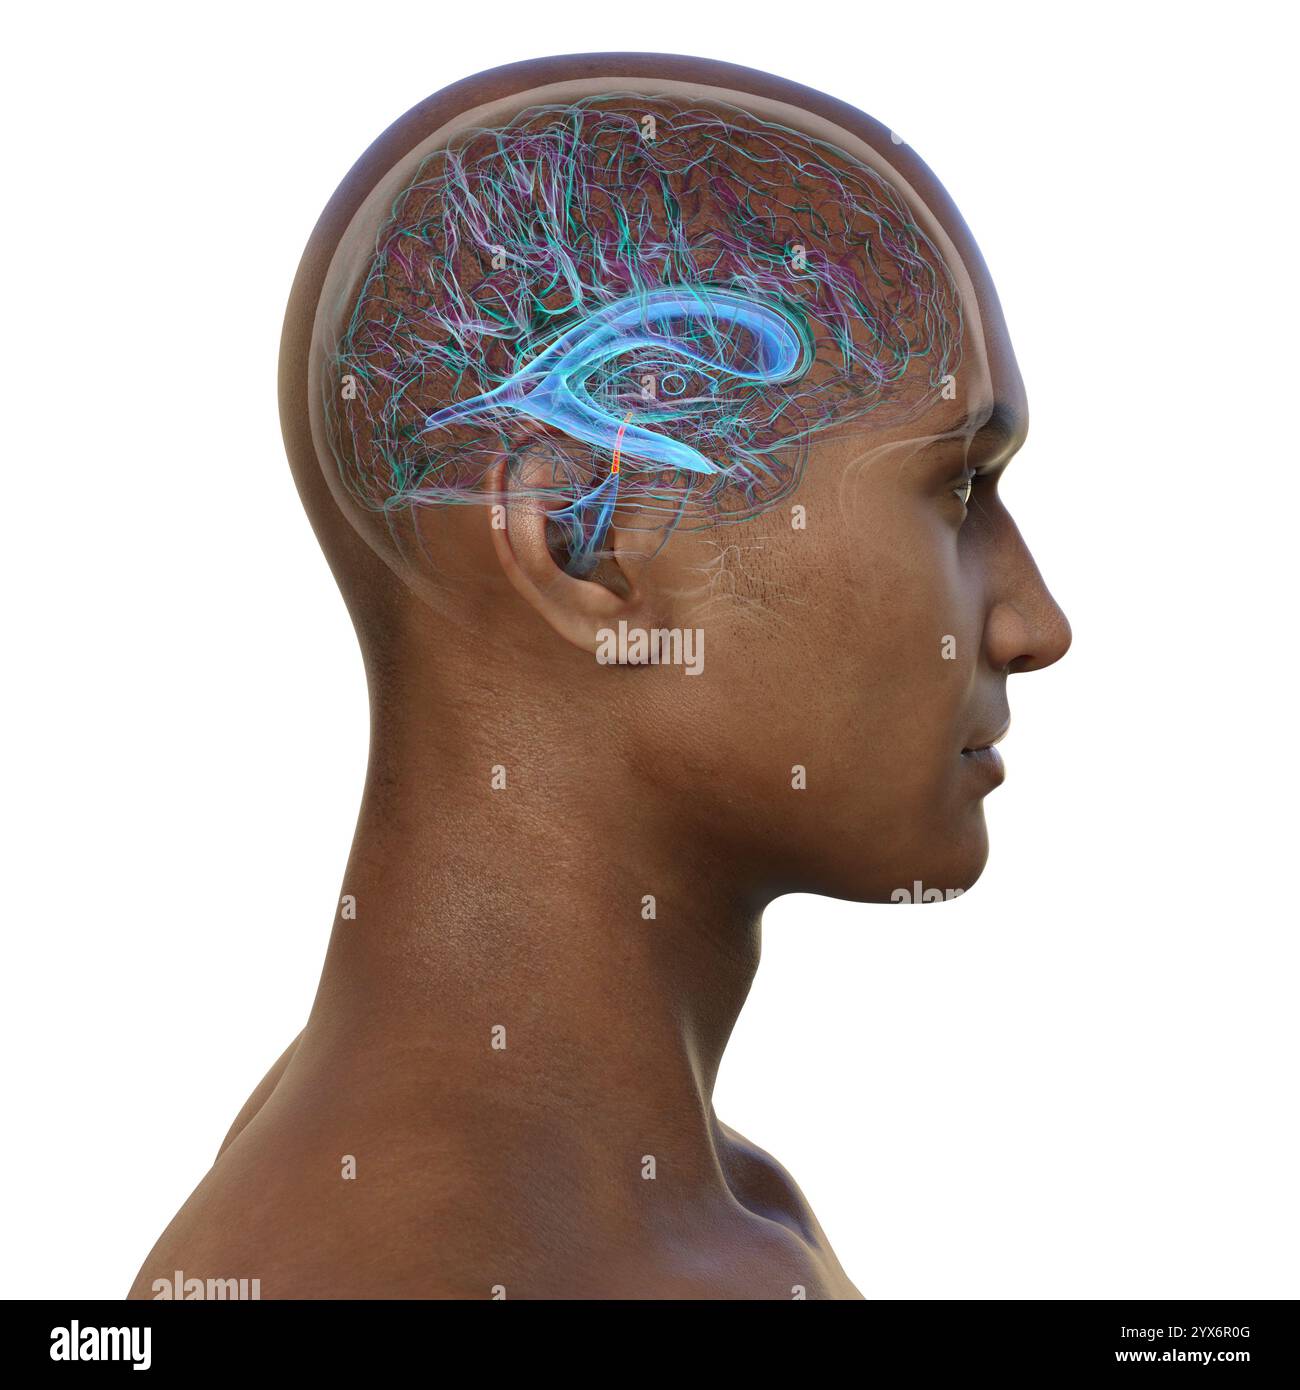

RF2T7NGWH–Ventrikel und zerebrales Aquädukt laterale Röntgenansicht 3D-Rendering-Illustration. Menschliches Gehirn und Ventrikelsystem Anatomie, Medizin, Gesundheitswesen, Scienc

RF2YX6R0N–Computerdarstellung des menschlichen Gehirns mit orangefarbenem Aquädukt und grünem Ventrikelsystem, die den Liquorfluss (CSF) zeigen.

RM2AWFNN9–Menschliche Anatomie, einschließlich Struktur und Entwicklung und praktische Überlegungen d in einem sagittalen mesialen Abschnitt (Abb. 910) wird jede dieser Teilungen als mit einem Teil des Systems der Kommunikation von Räumen verwandt angesehen, die als die dritten Ventrikel des Lateralands, der Aquädukt von Sylvius und der vierte Ventrikel die oben genannten Gehirnhemisphären ausdehnen. Durch den Hirnstamm und unter dem Kleinhirn bis zum zentralen Kanal des Rückenmarks. Da die lateralen Ventrikel zwei innumerieren, ist die Theirstellung im Zusammenhang mit den Gehirnhemisphären, in denen sie liegen, lateral zum m